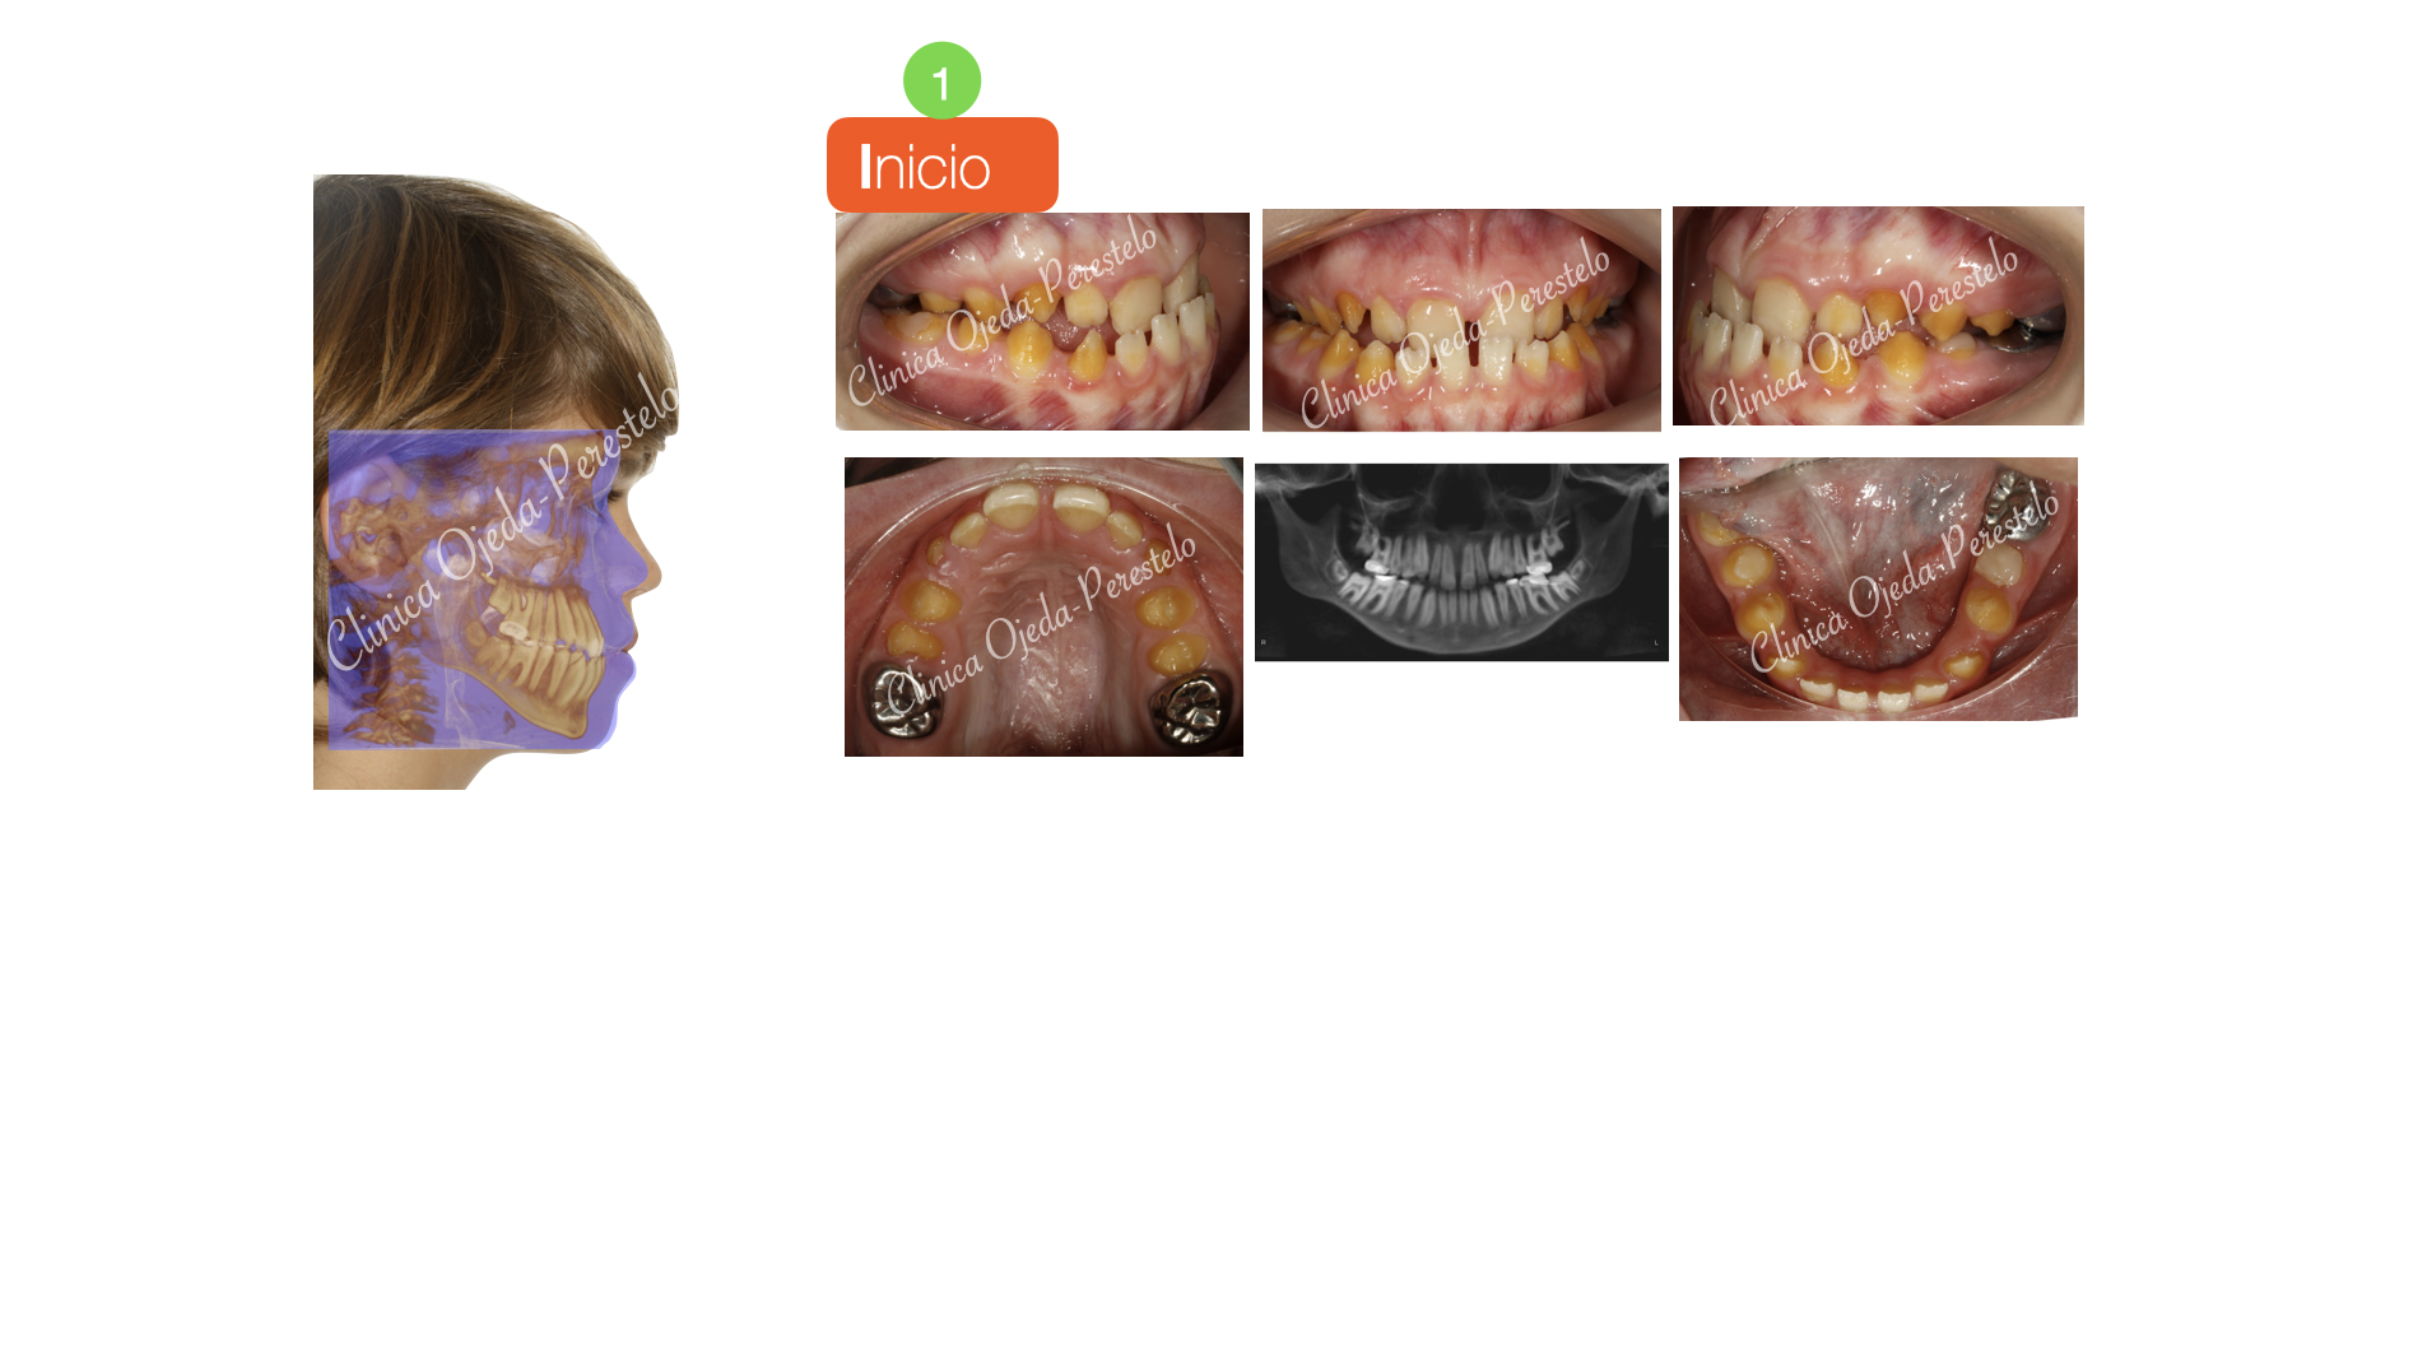

Paciente niño en dentición definitiva con amelogénesis imperfecta y clase III esquelética tratado con Ortopedia Maxilar . Se decidió colocar Miniplacas en la Mandíbula y en los Arbotantes Cigomáticos. En este caso la normalización espacial de los maxilares fue posible por el estímulo de los elásticos conectados a las Miniplacas. El impacto facial alcanzado con esta estrategia ha sido equivalente a una intervención quirúrgica de los Maxilares (Cirugía ortognática).

El paciente descartó continuar con una segunda fase de Ortodoncia,decidiendo disimular con un masking dental el color de sus piezas dentales.

Quisieramos destacar la mejoría experimentada en la estética facial y dentaria . Además se ha observado un aumento en el grado de permeabilización de la Vía Aérea y en la calidad del sueño del paciente.